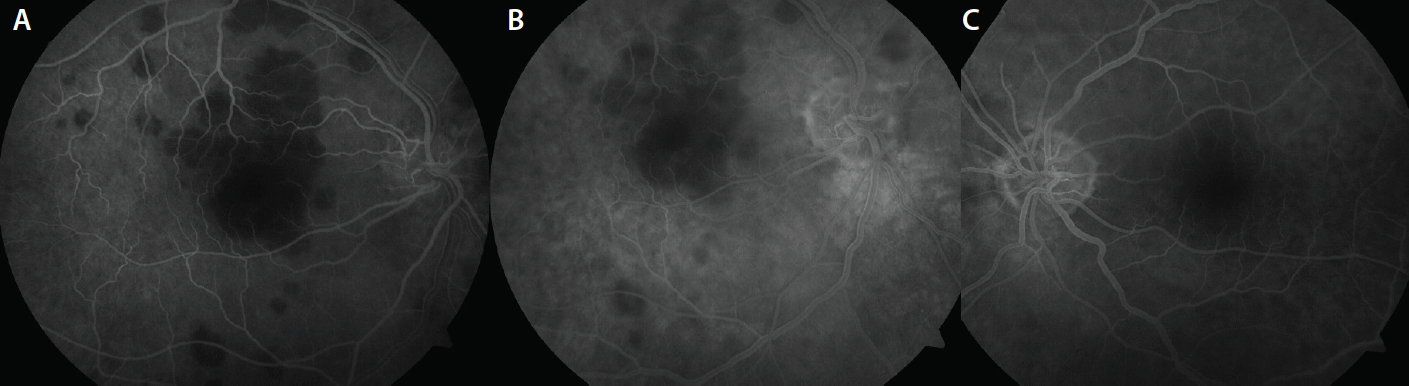

Spectral-domain optical coherence tomography demonstrated increased reflectivity of the outer retina in an area corresponding with the macular lesions OD (Figure 2). In addition, the outer retinal bands, including the ellipsoid layer, were disordered. These changes corresponded to increased signal transmission into the choroid. Fluorescein angiography revealed hypofluorescent lesions deep to the retina in the early phases of the angiogram (Figure 3). There was minimal staining and no leakage of the lesions in the later phases.

Figure 3. Fluorescein angiography OD. Early phase demonstrates hypofluorescence of the lesions deep to the retina at 20 seconds (A) and minimal staining at 2 minutes (B). Fluorescein angiography OS shows absence of any hypofluorescent macular lesions (C).